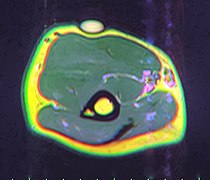

Diagnosis[edit | edit source]

A physical exam is typically the easiest way to diagnose it. Rarely, a tissue biopsy or imaging may be required. The imaging modality of choice is magnetic resonance imaging (MRI), because it has superior sensitivity of distinguishing it from liposarcoma as well as mapping the surrounding anatomy.[20]